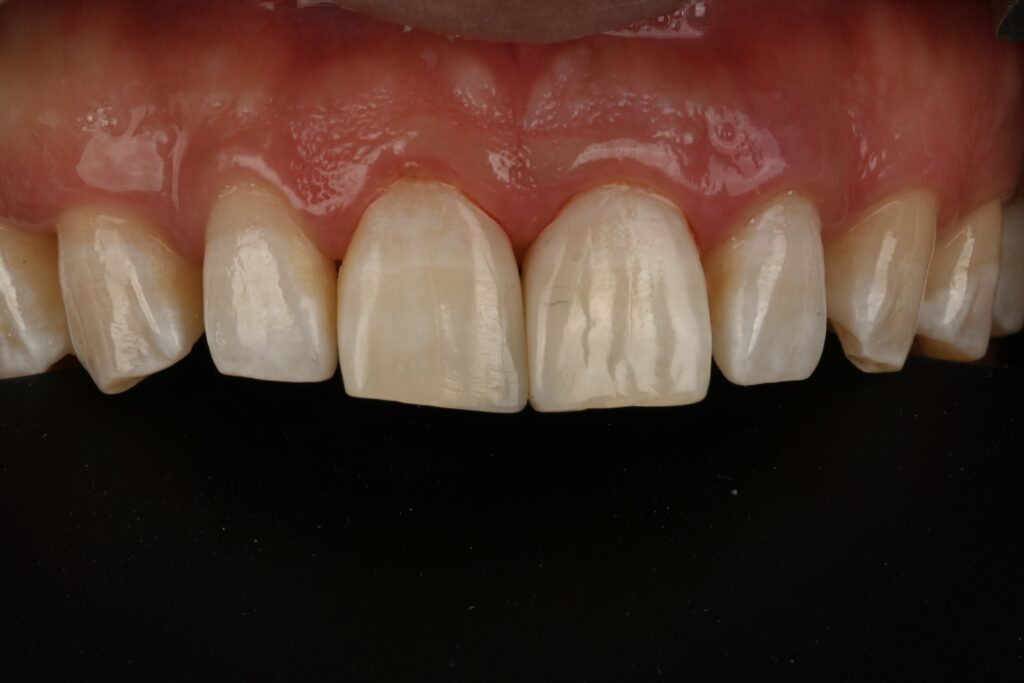

레진치료의 첫번째 조건 –완전한 방습으로 치료해야 합니다

방습을 시행하고 그리고 레진의 색상을 골라줍니다

레진은 다양한 색상이 있지만 사람의 치아는 그보다 더 다양한 색상을 가지고 있습니다

최대한 맞추어서 유사한 색상을 재현하는게 포인트이지요

그리고 치아의 형태를 잡아주는 바이오 클리어라는 재료가 필수입니다

이 재료가 나오고 나서 정말 레진치료가 좋아졌습니다

이렇게 형태를 잡아줄것으로 생각됩니다

하나씩 재현해 나가는 과정입니다

바이오클리어만으로 할수 있는 치료는 아니구요

수많은 조합이 있기 때문에 여기서 술자의 노하우가 필요한 치료 과정입니다

그리고 시간이 굉장히 많이 소요되는 술식입니다

1차적인 형태가 잡히는 과정입니다

대햑적인 형태를 잡고 그리고 길이 모양 형태를 수정합니다